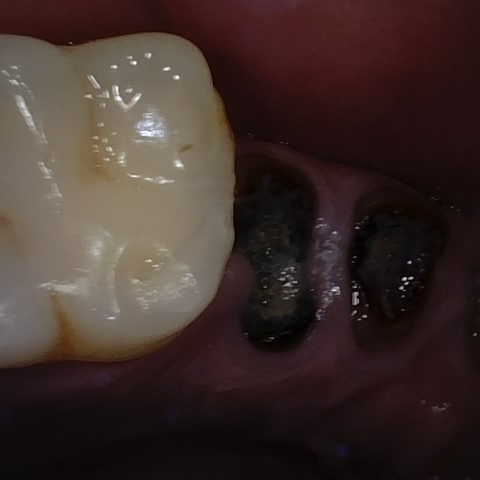

Annotated as "Good"